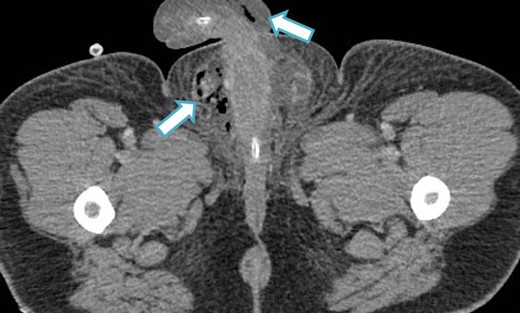

An urgent scrotal ultrasound demonstrated evidence of gas within the deep tissues of the scrotum but no abscess as shown in Fig. 1. Subsequently an abdomino-pelvic CT scan revealed multi-loculated collections in the right iliac fossa, suggesting perforated appendicitis with secondary extension of gas down the spermatic cord into the scrotum, as shown in Figs 2 and 3.

CT image (coronal slice) showing gas tracking from the right iliac fossa, down the spermatic cord into the scrotum.